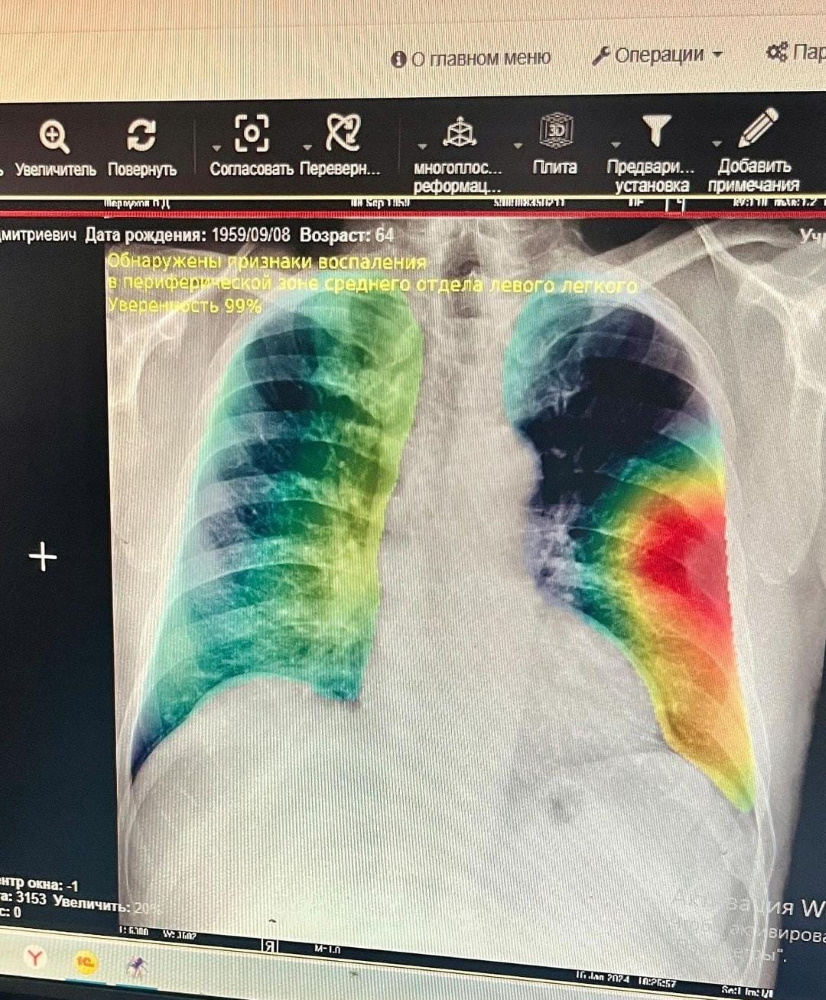

"Қазақ онкология және радиология ғылыми-зерттеу институты" АҚ-мен ("ҚазОРҒЗИ" АҚ) бірлесіп PneumoNet - жасанды интеллект (ЖИ) нейрожелісінің моделі әзірленіп, жүйеге енгізілді. Ол пациенттердің рентген-суреттерін талдайды және өкпеде күдікті учаскелерді бөліп көрсетеді, тіпті 74% дәлдікпен алдын ала қорытынды береді, сондай-ақ LungCancerCT - жасанды интеллект (ЖИ), пациенттердің КТ зерттеулерін талдайды және 3 мм-ден үлкен түйіндер мен түзілімдерді анықтайды.